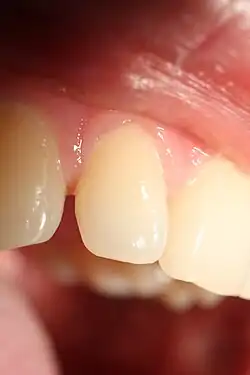

Kosmetisch störender, weiter Approximalraum im Bereich der Frontzähne

Bei Restaurationen wie Zahnfüllungen, künstlichen Zahnkronen oder Zahnersatz muss der Approximalkontakt wiederhergestellt werden. Bei Fehlen des Approximalkontakts oder bei zu schwacher Ausprägung können sich die Nachbarzähne verschieben und Nahrungsbestandteile oder Speisereste zwischen den Zähnen ins Zahnfleisch einschieben und dadurch dauerhaft schädigen. Aufgrund der erschwerten Reinigungsbedingungen kann sonst im Approximalraum das Entstehen einer Approximalkaries begünstigt werden. Im Frontzahnbereich sind schwarze Dreiecke (Black triangle disease)[3] im Bereich des Approximalraums kosmetisch störend, so dass in diesem Fall bei rekonstruktiven Maßnahmen der Approximalkontakt in Richtung Zahnfleischsaum verlängert wird.[4]